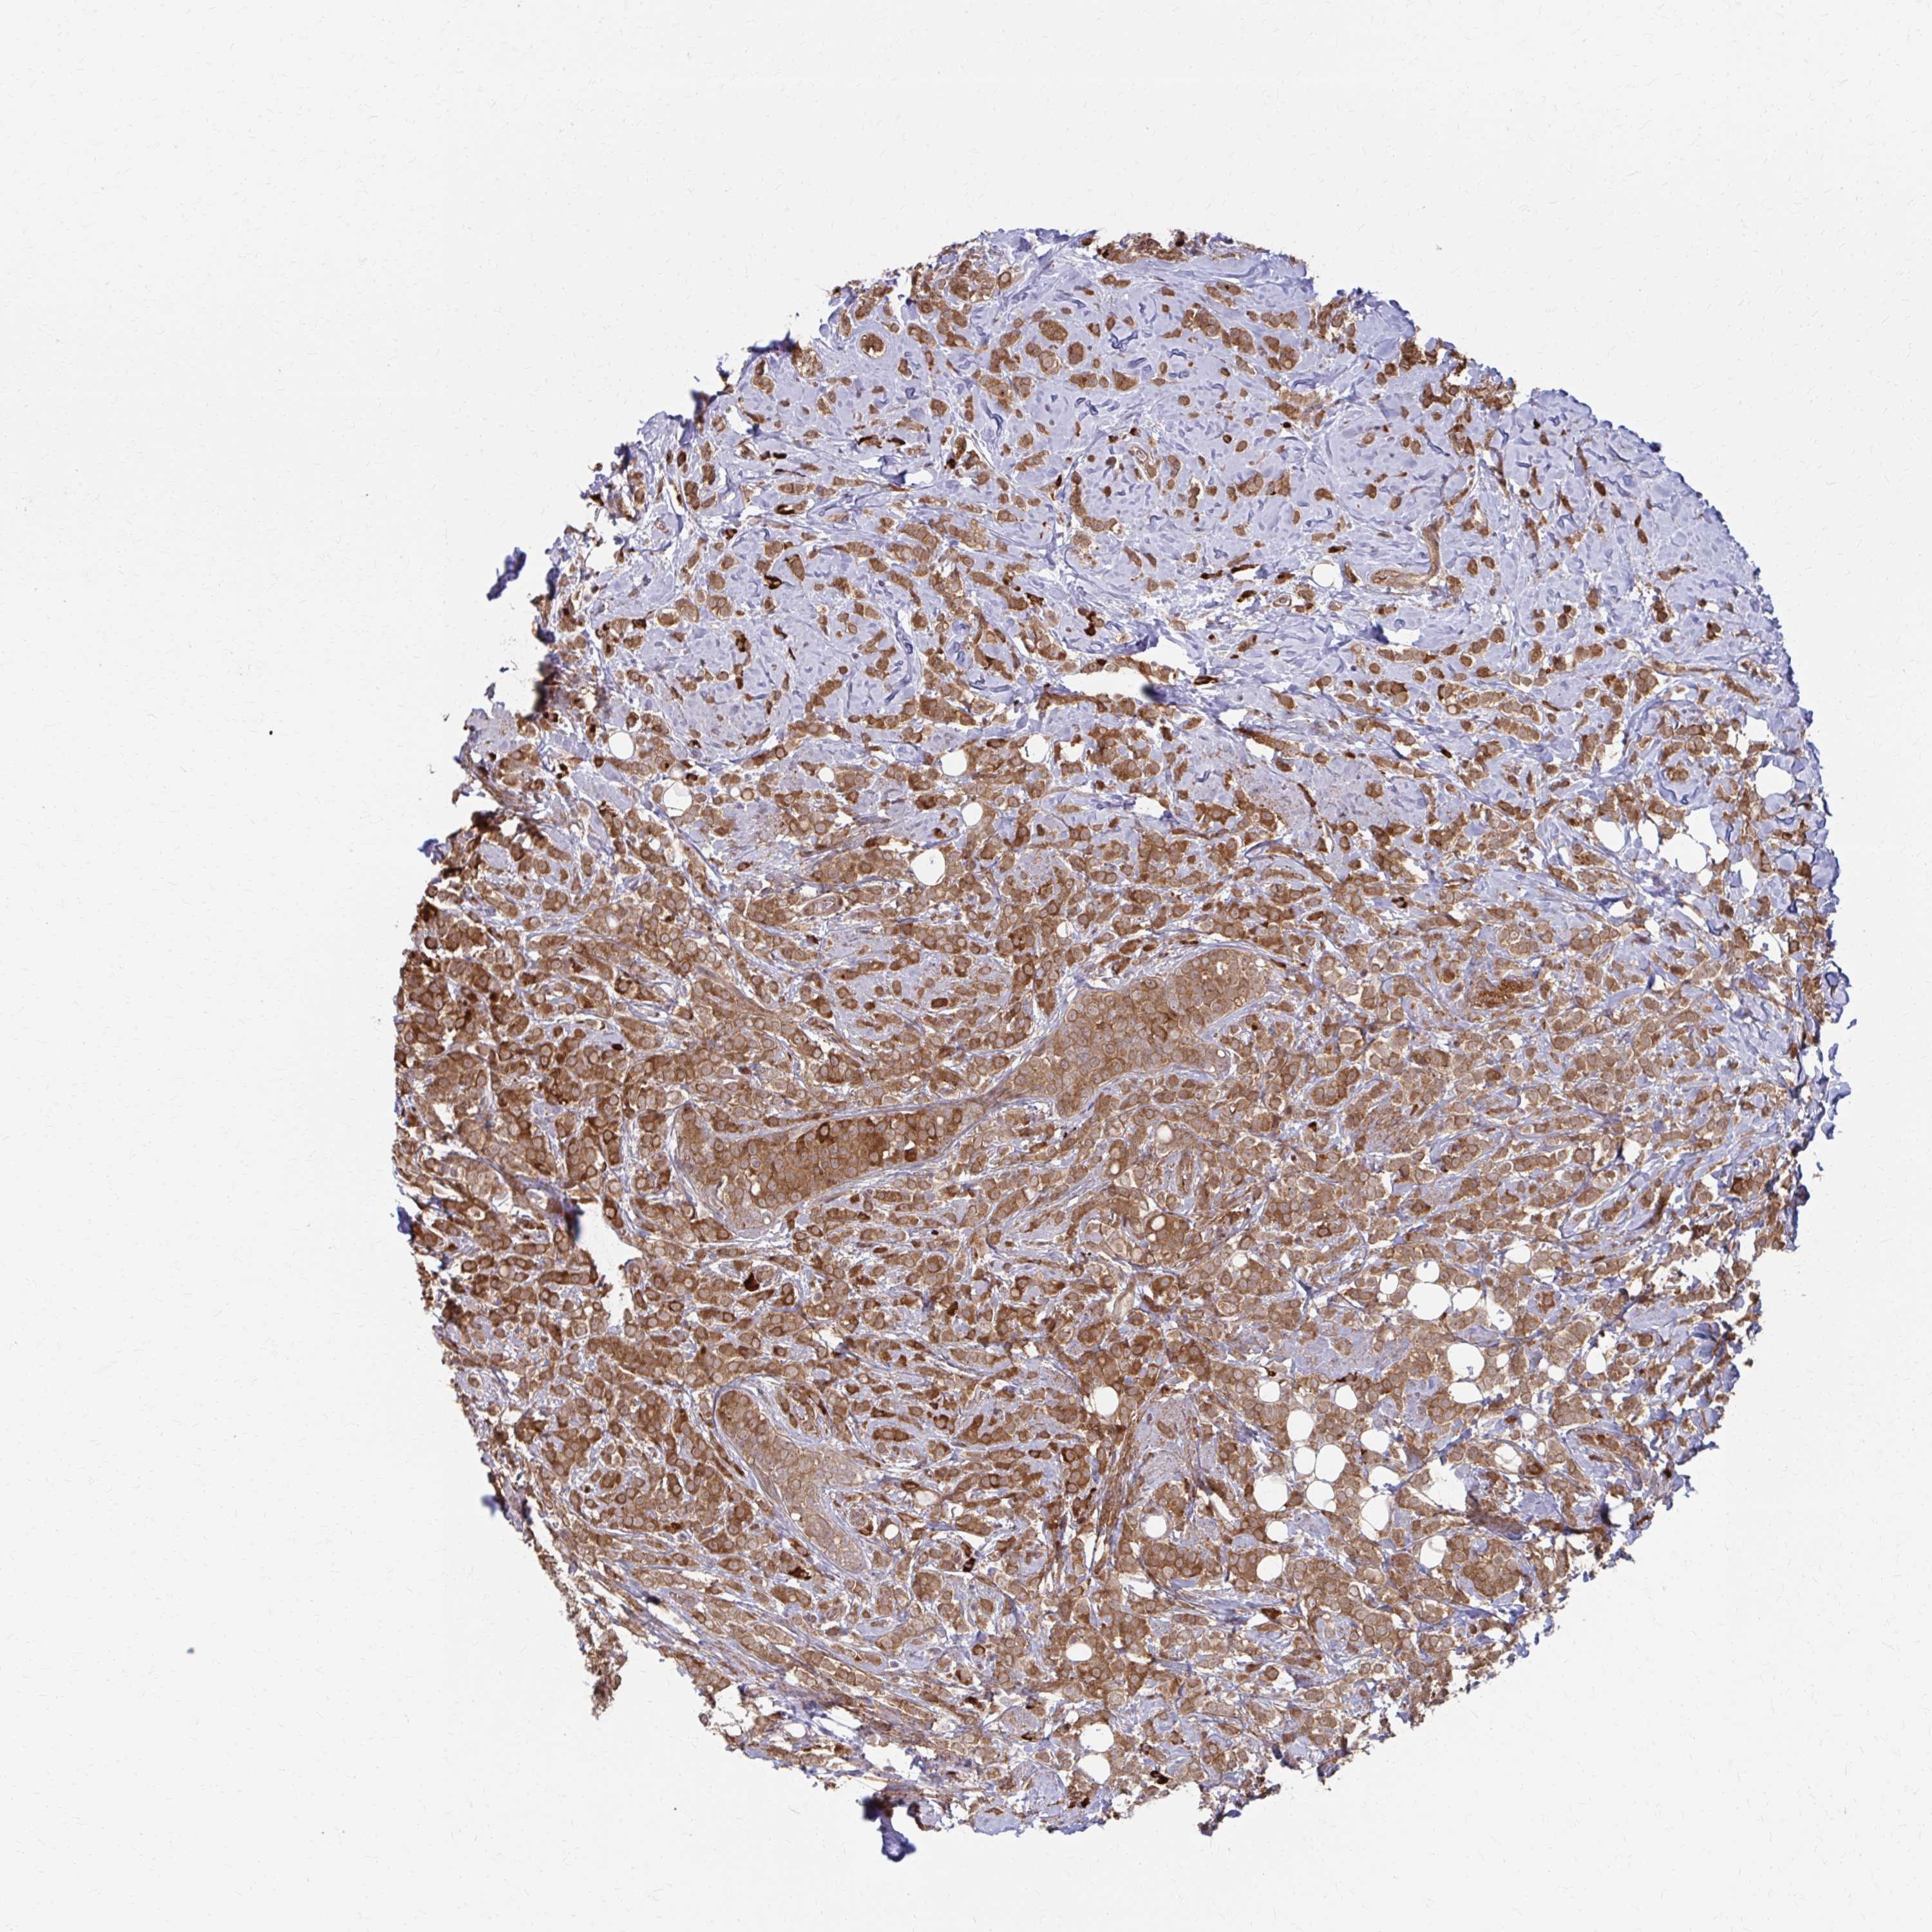

CANCER BREAST CANCER Show tissue menu

BRCA TCGA BRCA VALIDATION PROTEIN EXPRESSION